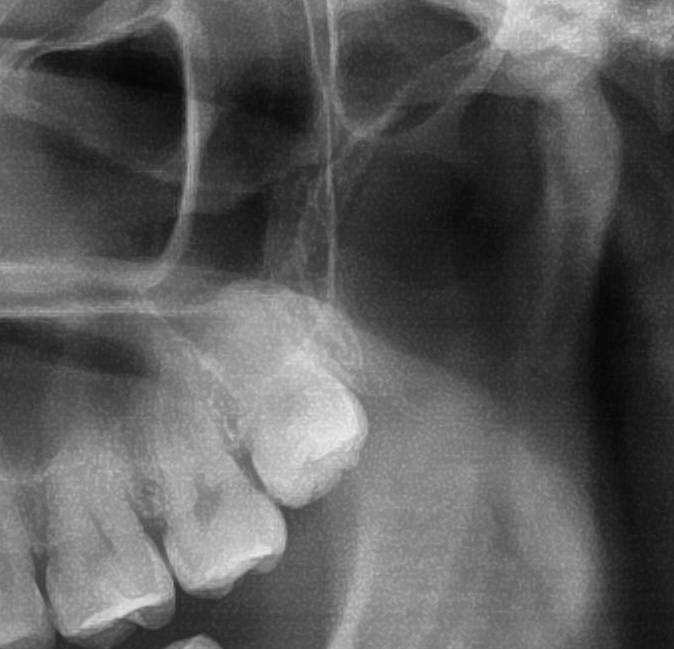

パノラマ写真を撮影してみると、左上の親知らずは歯茎に埋まってはいますが、ほぼまっすぐ生えているのが確認できました。

さらに、上顎の親知らずは上顎洞(副鼻腔)に近接して生えている場合もあるため、CTを撮影して位置関係を詳しく解析します。

上顎の親知らずが上顎洞(副鼻腔)に近い位置に生えている場合や、上顎洞へ突き抜けている可能性がある場合は、大きな病院に紹介する場合もあります。

今回は上顎洞からも距離があるため、抜歯は可能と診断されました。